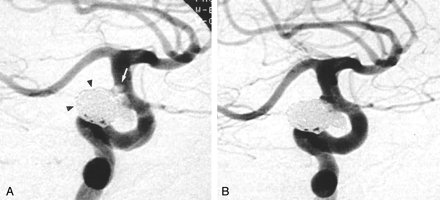

Images from the case of a 57-year-old female patient with a superior hypophyseal artery aneurysm.

A, Control angiogram of the right internal carotid artery, contralateral transorbital oblique projection. The superior hypophyseal artery aneurysm is tightly packed with GDCs (arrowheads). Thrombus has formed at the coil-parent artery interface, manifesting as a filling defect with a lobular contour with hazy margins (white arrow).

B, Control angiogram obtained 10 minutes after the administration of the Integrilin bolus shows resolution of thrombus at the coil-parent artery interface.